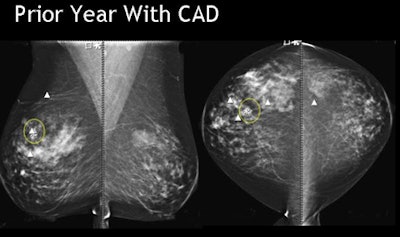

| Breast cancer detected by CAD in prior year's mammogram was ignored by the reader. All images courtesy of Dr. Stamatia Destounis. |

The study evaluated the effectiveness of digital mammography CAD in marking breast cancers both at diagnosis and in prior years' scans. The retrospective review examined all interval missed cancers from 2004-2008, Destounis said.

"CAD marked the area of cancer 47% of time (n = 24) on the prior most recent mammo, and in fact there was one case where the cancer was marked on two prior years," Destounis said. But in all cases of prior findings, either "we didn't pick it up or we didn't mark it," she said.

Overall, CAD marked the cancer 78% of the time, and cancer in prior year(s) 40% of the time, she said. So the study showed that even when CAD marked the lesion of interest, radiologists continue to disregard the CAD marks frequently, she said. Why is this happening?